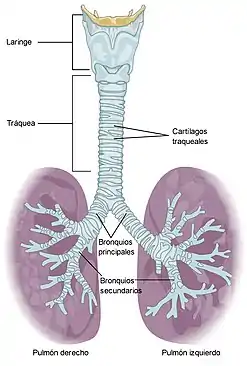

El órgano principal del aparato respiratorio humano y de los animales mamíferos es el pulmón. En los alveolos pulmonares se produce mediante difusión pasiva el proceso de intercambio gaseoso, gracias al cual la sangre capta el oxígeno atmosférico y elimina el dióxido de carbono (CO2) producto de desecho del metabolismo.[3] El aparato respiratorio humano está constituido por las fosas nasales, boca, faringe, laringe, tráquea y pulmones. Los pulmones constan de bronquios, bronquiolos y alveolos pulmonares.[4]

- Laringe: Es un conducto que permite el paso del aire desde la faringe hacia la tráquea y los pulmones. En la laringe se encuentran las cuerdas vocales que dejan entre sí un espacio llamado glotis.

- Tráquea: Es un conducto en forma de tubo que tiene la función de hacer posible el paso del aire entre la laringe y los bronquios. Su pared está reforzada por un conjunto de cartílagos con forma de C que dificultan que la vía se colapse por compresión externa sobre el cuello.[6]

- Pulmones: Órganos cuya función es realizar el intercambio gaseoso con la sangre. Dentro de cada pulmón, el árbol bronquial se divide progresivamente dando ramificaciones cada vez más pequeñas. La tráquea da origen a los dos bronquios principales que se dividen en bronquios secundarios o lobulares. Cada bronquio lobular se divide en bronquios terciarios o segmentarios que se dividen en bronquiolos. El bronquiolo continúa el proceso de ramificación y da origen al bronquiolo terminal de donde parten los bronquiolos respiratorio que es donde se encuentran los sacos alveolares.

- Bronquio: Conducto tubular fibrocartilaginoso que conduce el aire desde la tráquea hasta los bronquiolos.

- Bronquiolo: Conducto que conduce el aire desde los bronquios hasta los alvéolos.